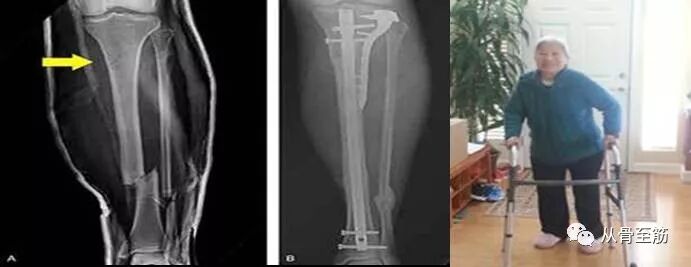

? ?做手术的患者手术中、手术后发生的异常情况一般叫并发症,不能称之为后遗症。还是回到最一开始的那位病人。踝关节粉碎性骨折,如果不手术治疗将会因为关节面不平、关节关系紊乱,最终会出现创伤性关节炎、关节疼痛甚至不能负重行走等后遗症。手术的目的是恢复正常解剖关系,以最大限度减少后遗症的发生。但手术也存在并发症的可能,如皮肤坏死、感染、骨髓炎、血管或神经损伤等等,当然医生会尽最大努力规避这些并发症。如果通过手术,关节面完全恢复,骨折复位良好并顺利愈合,但仍存在关节疼痛或行走受限,这不是手术造成的,是伤情严重,留下了后遗症。如果不手术,后遗症将更严重。?